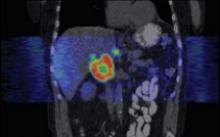

June 27, 2007 - Imaging Diagnostic Systems Inc. announced the release and publication of select results highlighting the advantages of using CT laser breast imaging as an adjunct to conventional mammography to improve detection of occult cancers in dense breasts.

"These CTLM results are being released as a response to the growing number of requests for performance statistics received from distributors and prospective customers worldwide. The results were obtained from our initial PMA-designed clinical study," commented Tim Hansen, IMDS Chief Executive Officer.